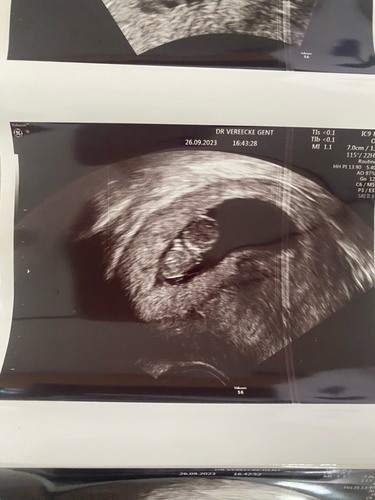

9+2 inwendig van rugaanzicht. Baby was lekker veel met zijn armpjes en beentjes aan het bewegen, zo leuk om te zien 🥰